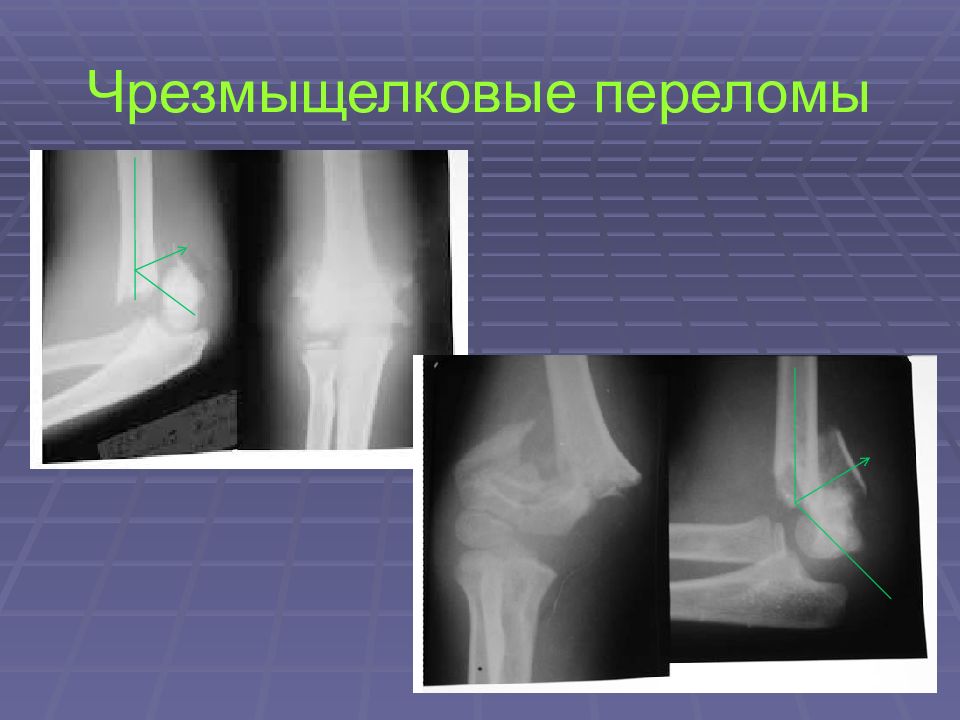

Слайд 19: Чрезмыщелковые переломы

Слайд 20: Чрезмыщелковые переломы

Разгибательный перелом ( угол между отломками открыт кзади )

Слайд 21: Чрезмыщелковые переломы

Слайд 22: Чрезмыщелковые переломы

Сгибательный перелом ( угол между отломками открыт кпереди)

Слайд 23: Чрезмыщелковые переломы

Слайд 24: Чрезмыщелковые переломы

Слайд 25: Чрезмыщелковые переломы

Осложнения: Неврологические нарушения Ишемические расстройства Контрактуры локтевого сустава Параартикулярные оссификаты Посттравматические деформации локтевого сустава